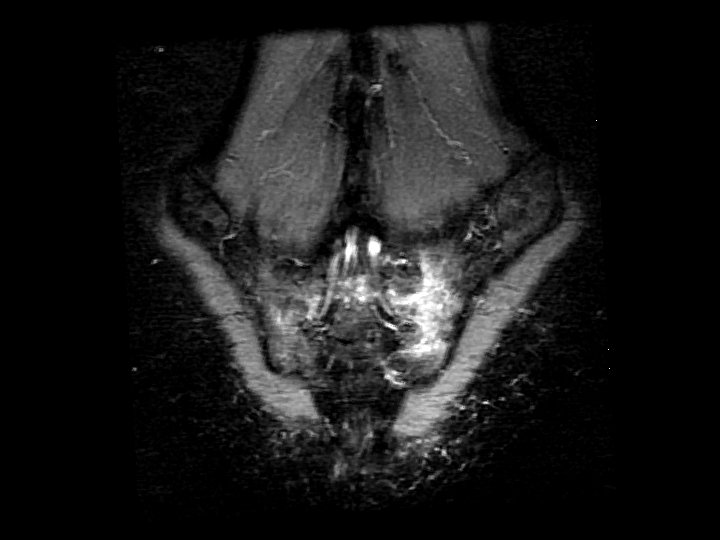

Sacral Insufficiency Fracture • Findings: – High T 2 signal in the left sacral ala crossing the midline and involving the right side • Normal stress on abnormal bone (usually osteoporosis) • Pts can have non-specific back or hip pain • Plain films show lucency, then sclerosis • Bone scan show classic “Honda sign” • ddx: – acute fractures – metastases